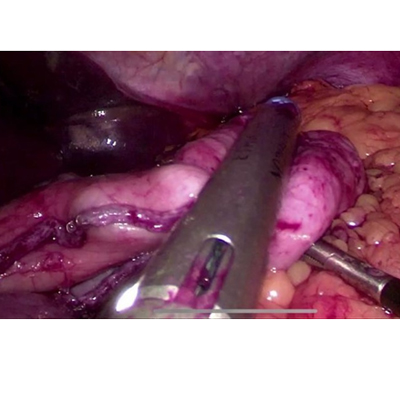

LAPAROSCOPIC SURGERY FOR PANCREATIC TUMOUR

LAPAROSCOPIC SURGERY FOR RECTAL CANCER

LAPAROSCOPIC WHIPPLES PROCEDURE

We have state of the art operating theatre with advanced surgical equipments. We have a Karl Storz Spies advanced HD laparoscopy operating system in addition to a 3 chip laparoscopy. We have installed advanced vessel sealing devices like Gen 11 harmonic scalpel, Ligasure from Valley Lab & Argon plasma coagulator. There is a recent addition of Cavitron Ultrasonic Aspirator (CUSA) system into our surgical armamentarium. We have the most recent powered Echelon endo-stapling devices. In addition to all these we have a constant supply of various types of advanced stapling devices for GI surgeries. Our endoscopy machines are having high definition with FICE Technology. Last but not the least we have semi flexible Ureteroscopy for managing common bile duct stones.